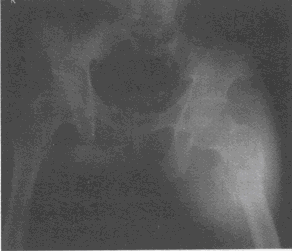

患者男,40岁,患者因"高处坠落致左髋部疼痛、畸形,活动受限2天"入院,左下肢屈曲外展畸形,外旋近90°,左髋部肿胀,左股骨大转子处压痛明显,左髋部可扪及骨擦感,左髋关节活动受限。行骨盆正位如下图所示:

(单选题)该患者骨折Evans改良分型应为()

A:Ⅱ型

B:Ⅲ型

C:Ⅳ型

D:Ⅴ型

E:Ⅰ型

(单选题)该骨折创伤的机制是()

A:低能量暴力

B:高能量暴力

C:病理性骨折

D:疲劳性骨折

E:骨质疏松